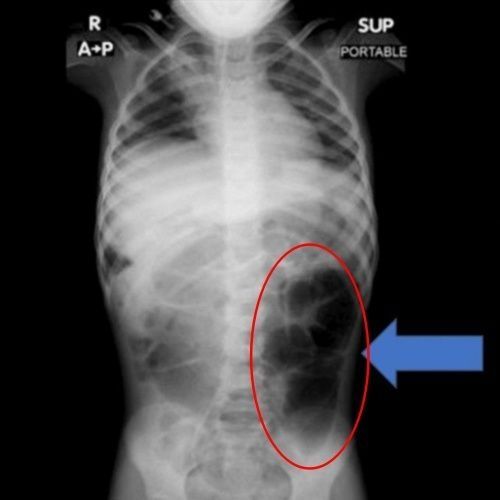

Recently, the medical journal Cureus reported on the case of a six-year-old girl living in Saudi Arabia. The girl, identified as patient A, visited the hospital after experiencing persistent abdominal pain and digestive problems.

A thorough examination of patient A's stomach revealed a mass formed by tangled hair inside the stomach. The hair was not confined to the stomach but extended into the small intestine. The medical team emphasized, "If a pediatric patient experiences prolonged abdominal pain, vomiting, and loss of appetite, the possibility of a foreign body in the gastrointestinal tract must always be considered."